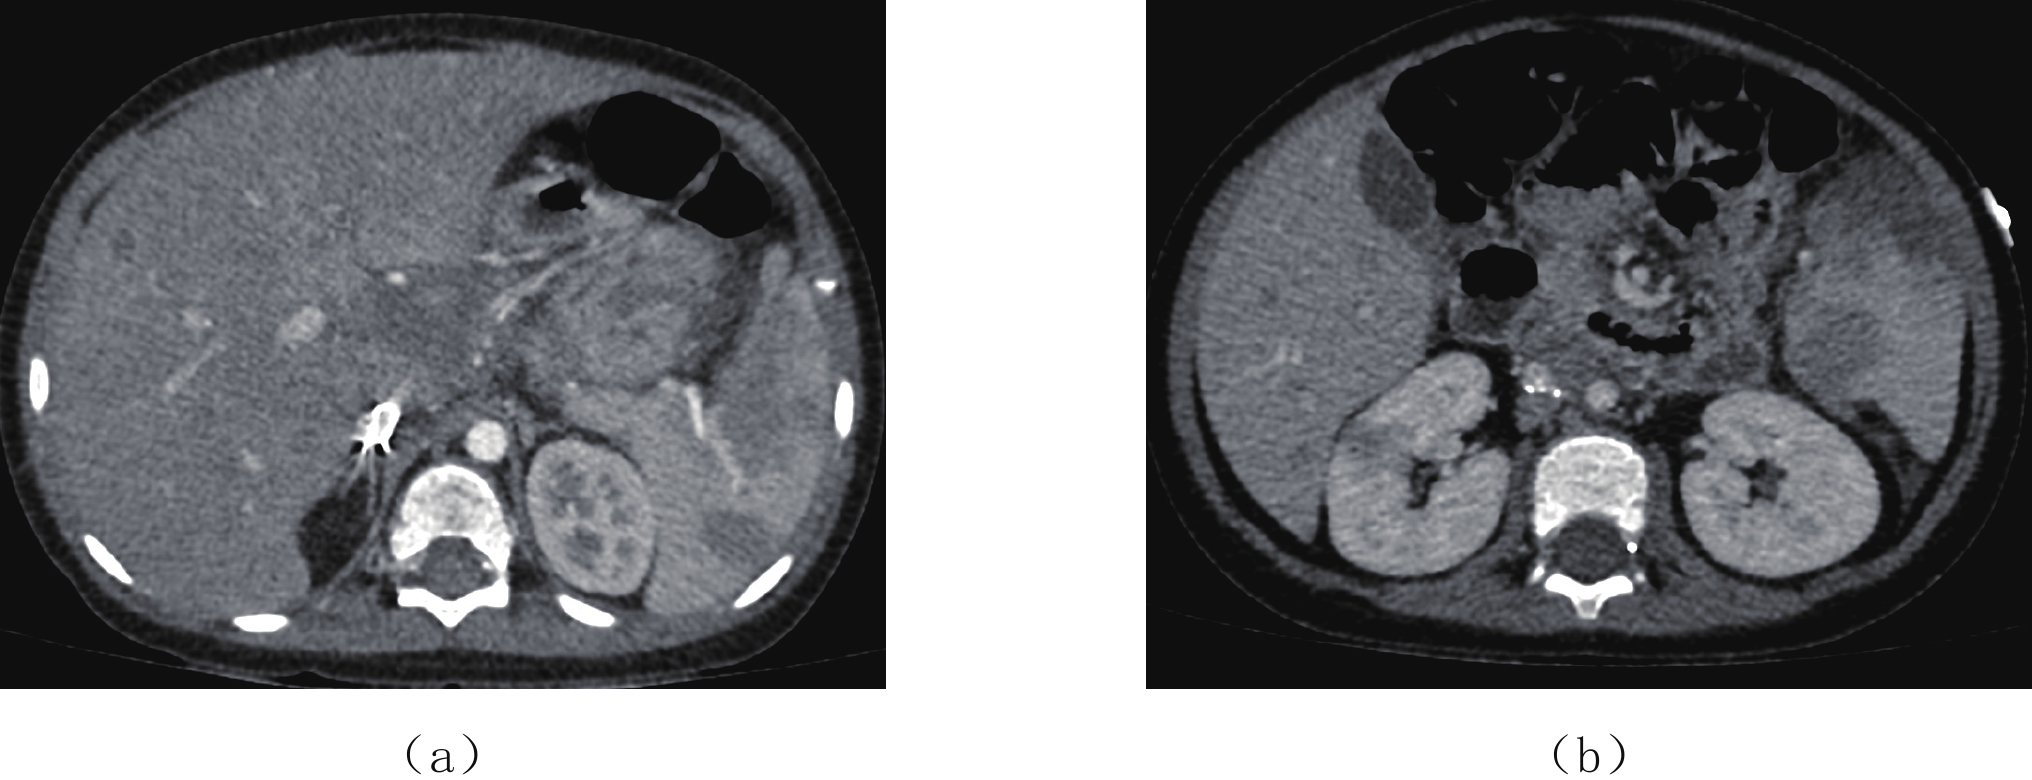

Epstein-Barr virus (EBV), also known as a gamma herpesviru, has the characteristics of lymphophilic tissue. EBV is one of the most common human viruses of the human cold virus group and the first human tumor virus found. Infection with EBV occurs by the oral transfer of saliva and respiratory secretions. Human B-lymphocytes and epithelial cells are EBV-susceptible host cells. First EBV infection often occurs in infancy and in childhood. EBV-associated diseases include infectious mononucleosis, EB virus associated hemophagocytic lymphoproliferative disorder (EBV-HLH), chronic active EBV Infection, EBV infection-associated autoimmune disease. EBV infection can also cause the proliferative diseases of the infected cells, such as various non-malignant lymphoproliferative diseases, lymphomatoid granulomatosis, EBV associated with many more malignant diseases including Burkitt′s lymphoma, Hodgkin′s lymphoma, Diffuse Large B-Cell Lymphoma, NK/T cell lymphoma, nasopharyngeal carcinoma, a subset of gastric carcinomas, and many more. This paper mainly focuses on EBV associated lymphoproliferative diseases and imaging characteristics in children.